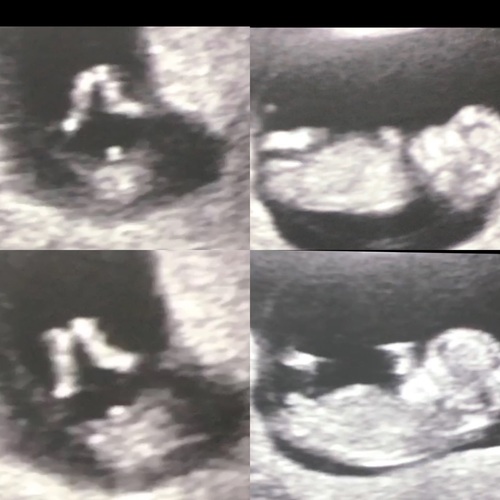

Wat denk je ! 馃槀

Haha duidelijk een jongen

11 weken hebben ze allebei n uitsteeksel ben benieuwd 馃槀馃槀馃槀

Dit heb ik dus ook maar het kan ook de navelstreng zijn zo verwarrend haha